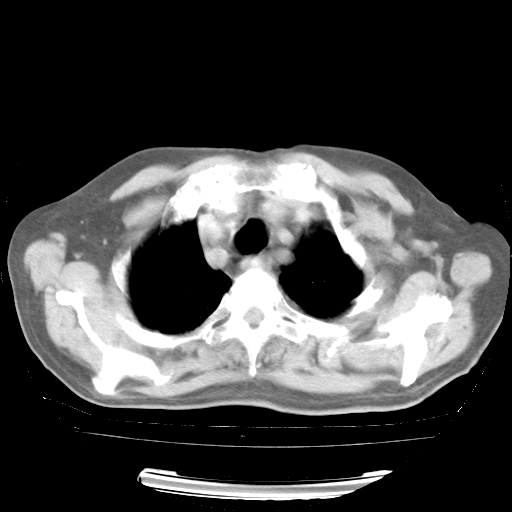

4月28日肺部CT——再次出现类似去年5月9日——透光度降低,“间质性”改变。

4月28日肺部CT